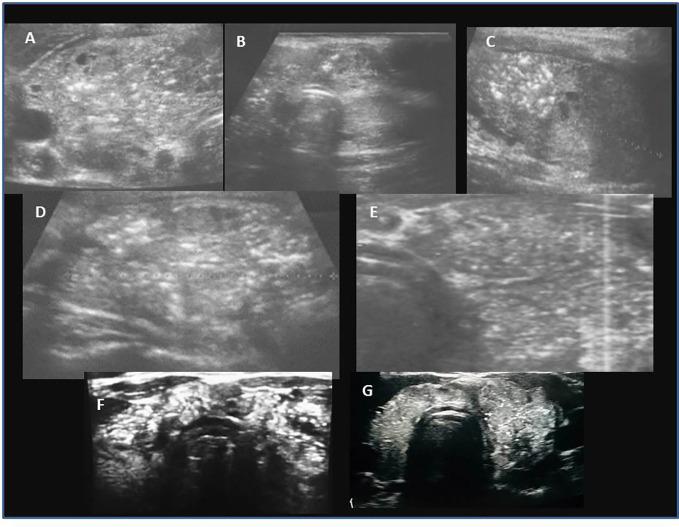

A retrospective analysis of medical records of 90 patients (69; 76.7% females). The mean age at PTC diagnosis was 13.8 years [range 6-18]. All patients were evaluated ultrasonographically before thyroid surgery. Thyroid nodules were categorised using the European Thyroid Imaging Reporting and Data System (EU-TIRADS PL), and cytopathology was assessed using Bethesda criteria. Neck ultrasound results and thyroid and autoimmune status were correlated with histopathological PTC assessment.

回顾性分析 90 例患者(69 例;女性占 76.7%)的病历。PTC 诊断时的平均年龄为 13.8 岁[6-18 岁]。所有患者均在甲状腺手术前进行超声检查。甲状腺结节采用欧洲甲状腺成像报告和数据系统(EU-TIRADS PL)进行分类,细针穿刺细胞学检查采用 Bethesda 标准评估。颈超声结果和甲状腺及自身免疫状态与组织病理学 PTC 评估相关。